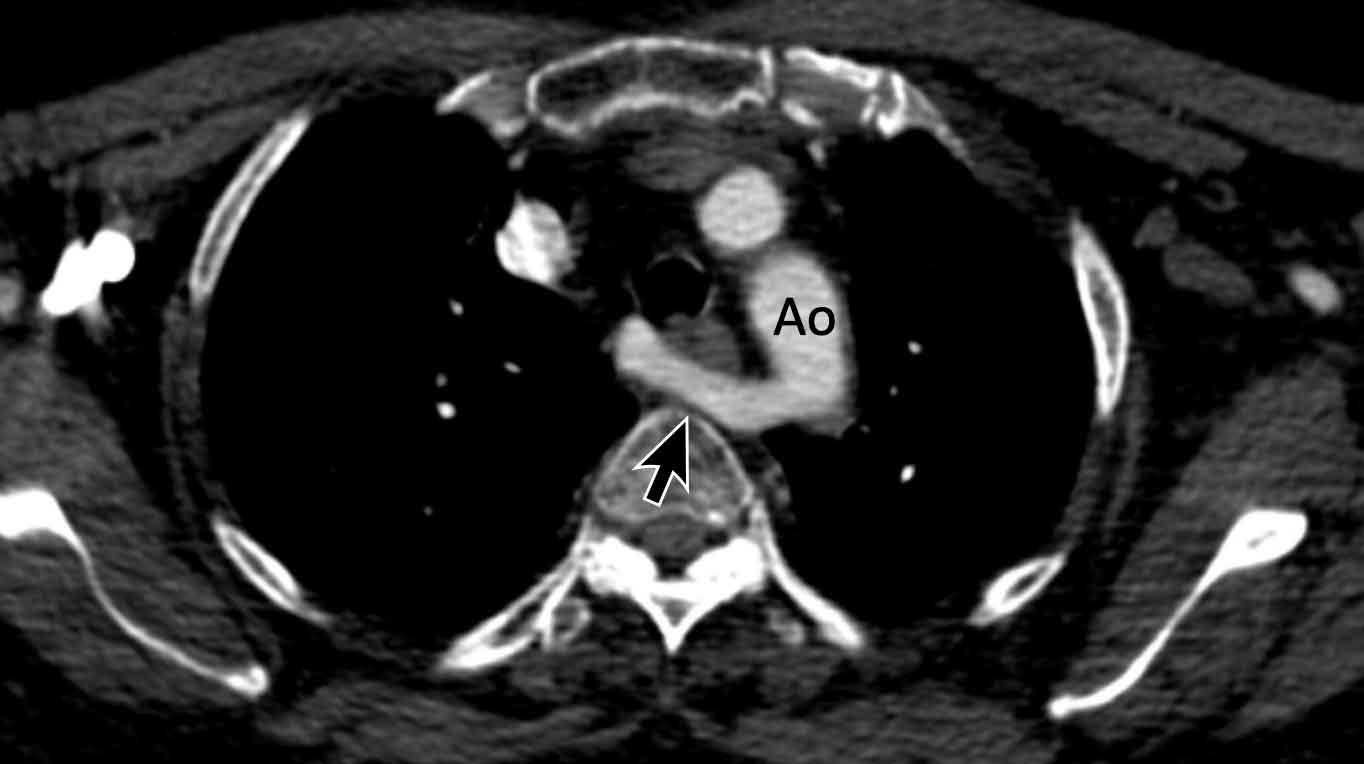

Hình ảnh

Sùi nhiễm khuẩn khổng lồ trên van ba lá ở một người dùng heroin qua đường tĩnh mạch bị viêm nội tâm mạc do S. Aureus.